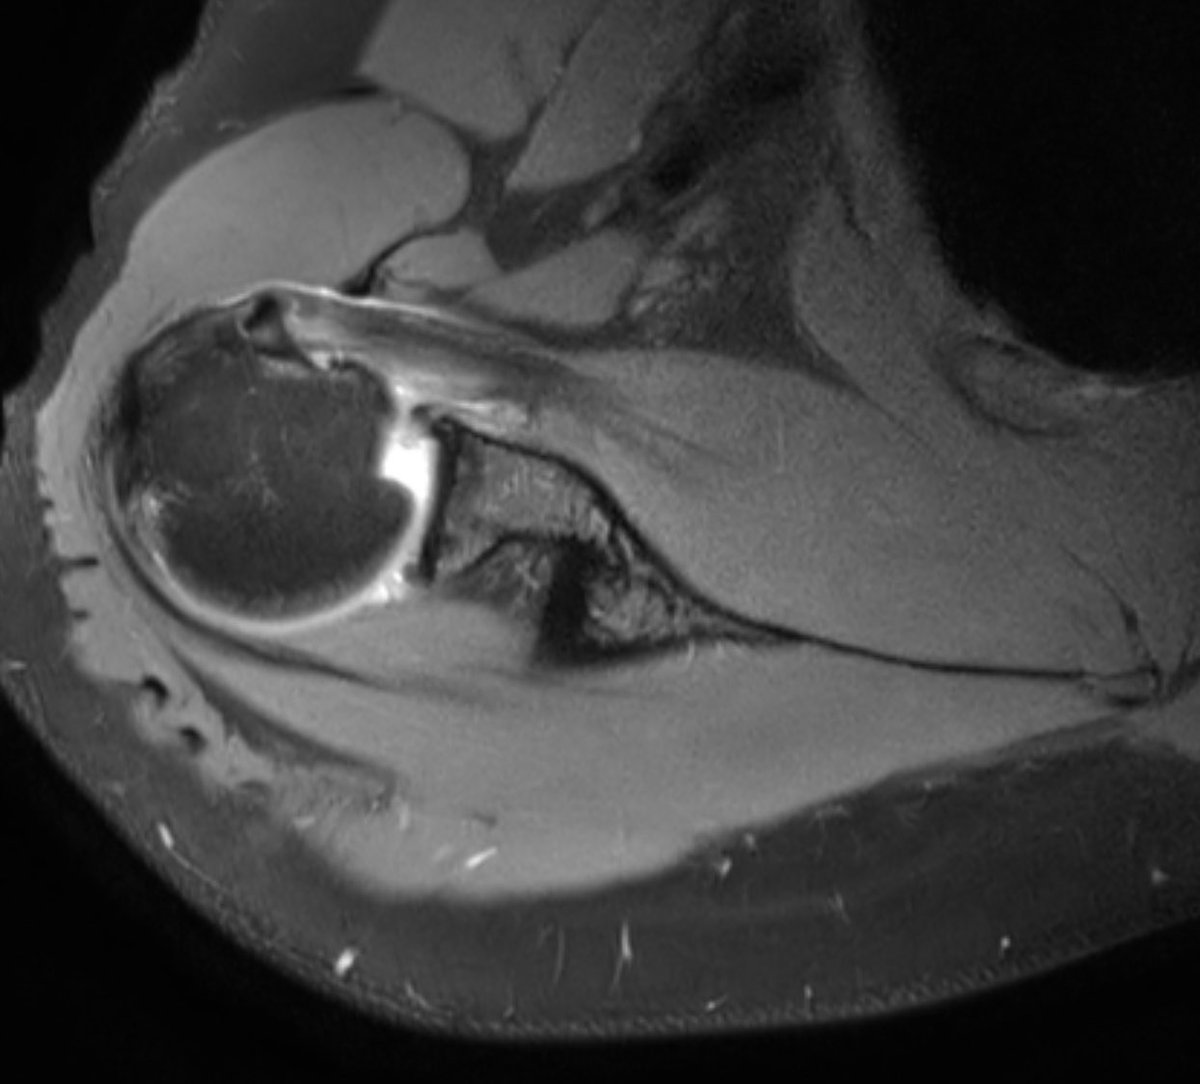

Consent ✅ Right hip pain & stiffness Both hip joints show OA changes - but R more advanced than L Why?

🕵️♂️ Dr. Murphey’s X-Files has arrived at Skeletal Radiology! 📂 Case #001 is now live. 👉 What’s the most likely diagnosis? 💡 Share your thoughts and come back to check the answer! Because, in the end, the truth is in the images. #SkeletalRadiology